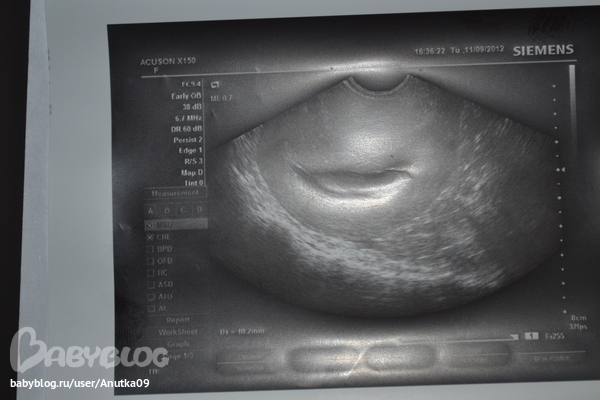

Выкладываю узи прошлое где видели эмбрион и серцебиение, и сегодняшнее где ставят анэмбрионию.... ну как такое может быть??? куда мог деться малыш за месяц???

я если честно второе узи вообще не разберу.... на сколько я вижу на первом и узистка другая тогда говорила что плод есть.... так куда он мог дется??

Я вообще не понимаю, что это такое на втором снимке. Это типо плодное яйцо так диформировалось? Бред какой то. А что конкретно УЗИстка сказала? Как такое может быть?

она написала: беременность 7 недель неразвивающаяся по типу анэмбрионии.

Я вижу в матке круглешочек и что-то в нем. Нужно мнение как минимум двух разных специалистов. Второму лучше ничего не говорить вначале. Только после его вердикта.

я тоже после твоих слов пригляделась. Что то есть. Дело в другом, что на таком сроке это уже эмбриончик должен быть, а не плодное яйцо. Но все равно - второй снимок какой-то калечный. Нихрена не видно(

Я скачала фотки н акомпьютер и хорошо увеличила, так вот я вижу и там и там эмбриончик, просто второй аппарат узи совсем другой и мог просто не так хорошо все это дело просветить. да плюс мне еще кажется еще результат узи зависит под каким углом датчик наклонили. Вообщем если был плод, обратно развиться он не мог, и как минимум он был бы на фото таких же размеров. А второе узи непонятное. Поэтому не слушайте никого, идите еще на узи, я думаю что все у вас Хорошо. Крепитесь.